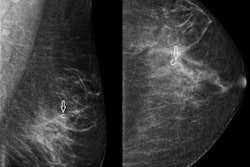

Breast cancer screening aims to detect breast tumors at a smaller size when they are more manageable and associated with a better prognosis. If that's true, the number of large cancers among women who are offered screening should fall and mortality should also decline, the authors explained.

Average tumor size decreased by 23% over the 32-year period, from 26 mm to 20 mm, but the trend was not consistent over the years and varied according to the women's ages, they found.

When breast screening was introduced in the early 1980s, the average size of breast cancers fell sharply. In women between the ages 70 and 74, the average size of tumors declined by 27%, but in women ages 85 and older, tumors declined only 10%. Average tumor size in these older women, who are less likely to be screened, remains the highest.

The researchers discovered an unexpected rise in average tumor size between 3% (in the 75 to 79 age group) and 13% (in the 50 to 54 age group) from 2001 to 2014.